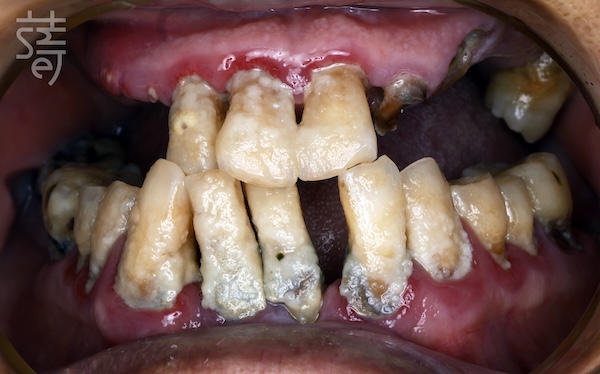

一開始,女兒替黃爸爸搜尋「水雷射牙周治療」,以為治好牙周病就能保住牙齒;

但檢查發現,上顎僅剩的牙幾乎都是爛牙根,若採傳統方式不僅曠日費時,費用也十分高昂,讓他心生退意。

At first, his daughter searched for “laser periodontal therapy,” thinking that treating gum disease might save his teeth. But the exam showed that nearly all his upper teeth were nothing more than decayed roots. Traditional treatment would have been long, invasive, and prohibitively expensive.

之後女兒找到 All-on-4 技術,卻因上顎骨幾乎完全流失,屢屢遭診所婉拒。

直到遇見蒔美牙醫錢世康醫師,提出 All-on-5 結合顴骨植體的方案,黃爸爸才終於看見重建的希望。

Later, she discovered the All-on-4 technique, but with his near-total loss of upper jawbone, clinic after clinic turned them away. Only when they met Dr. Shih-Kang Chien at Smile Dental Group—who proposed an All-on-5 plan reinforced with zygomatic implants—did real hope emerge.